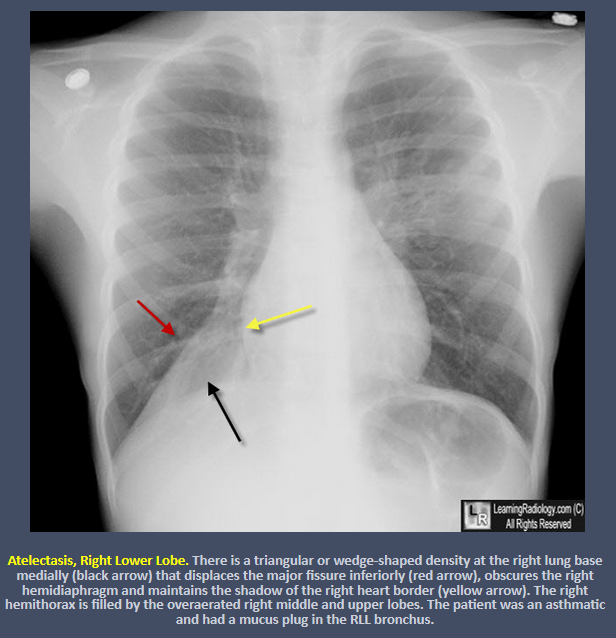

What are the signs of right lower lobe atelectasis?